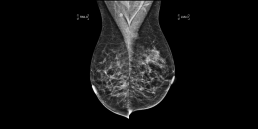

Dépistage en 2020. La densité mammaire est B.

Une asymétrie a été trouvée dans le sein gauche, dans le quadrant externe supérieur, à l’extrémité postérieure. La tomosynthèse a mis en évidence une masse spiculée à l’emplacement de l’asymétrie, à 9 cm du mamelon.

Il semble que la masse ait augmenté depuis les examens précédents.

La biopsie a confirmé qu’il s’agissait d’un carcinome canalaire in situ (DCIS), grade II.

MammoScreen repère très bien la masse spiculée dans la tomosynthèse donnant un score 9 de plus haute suspicion.